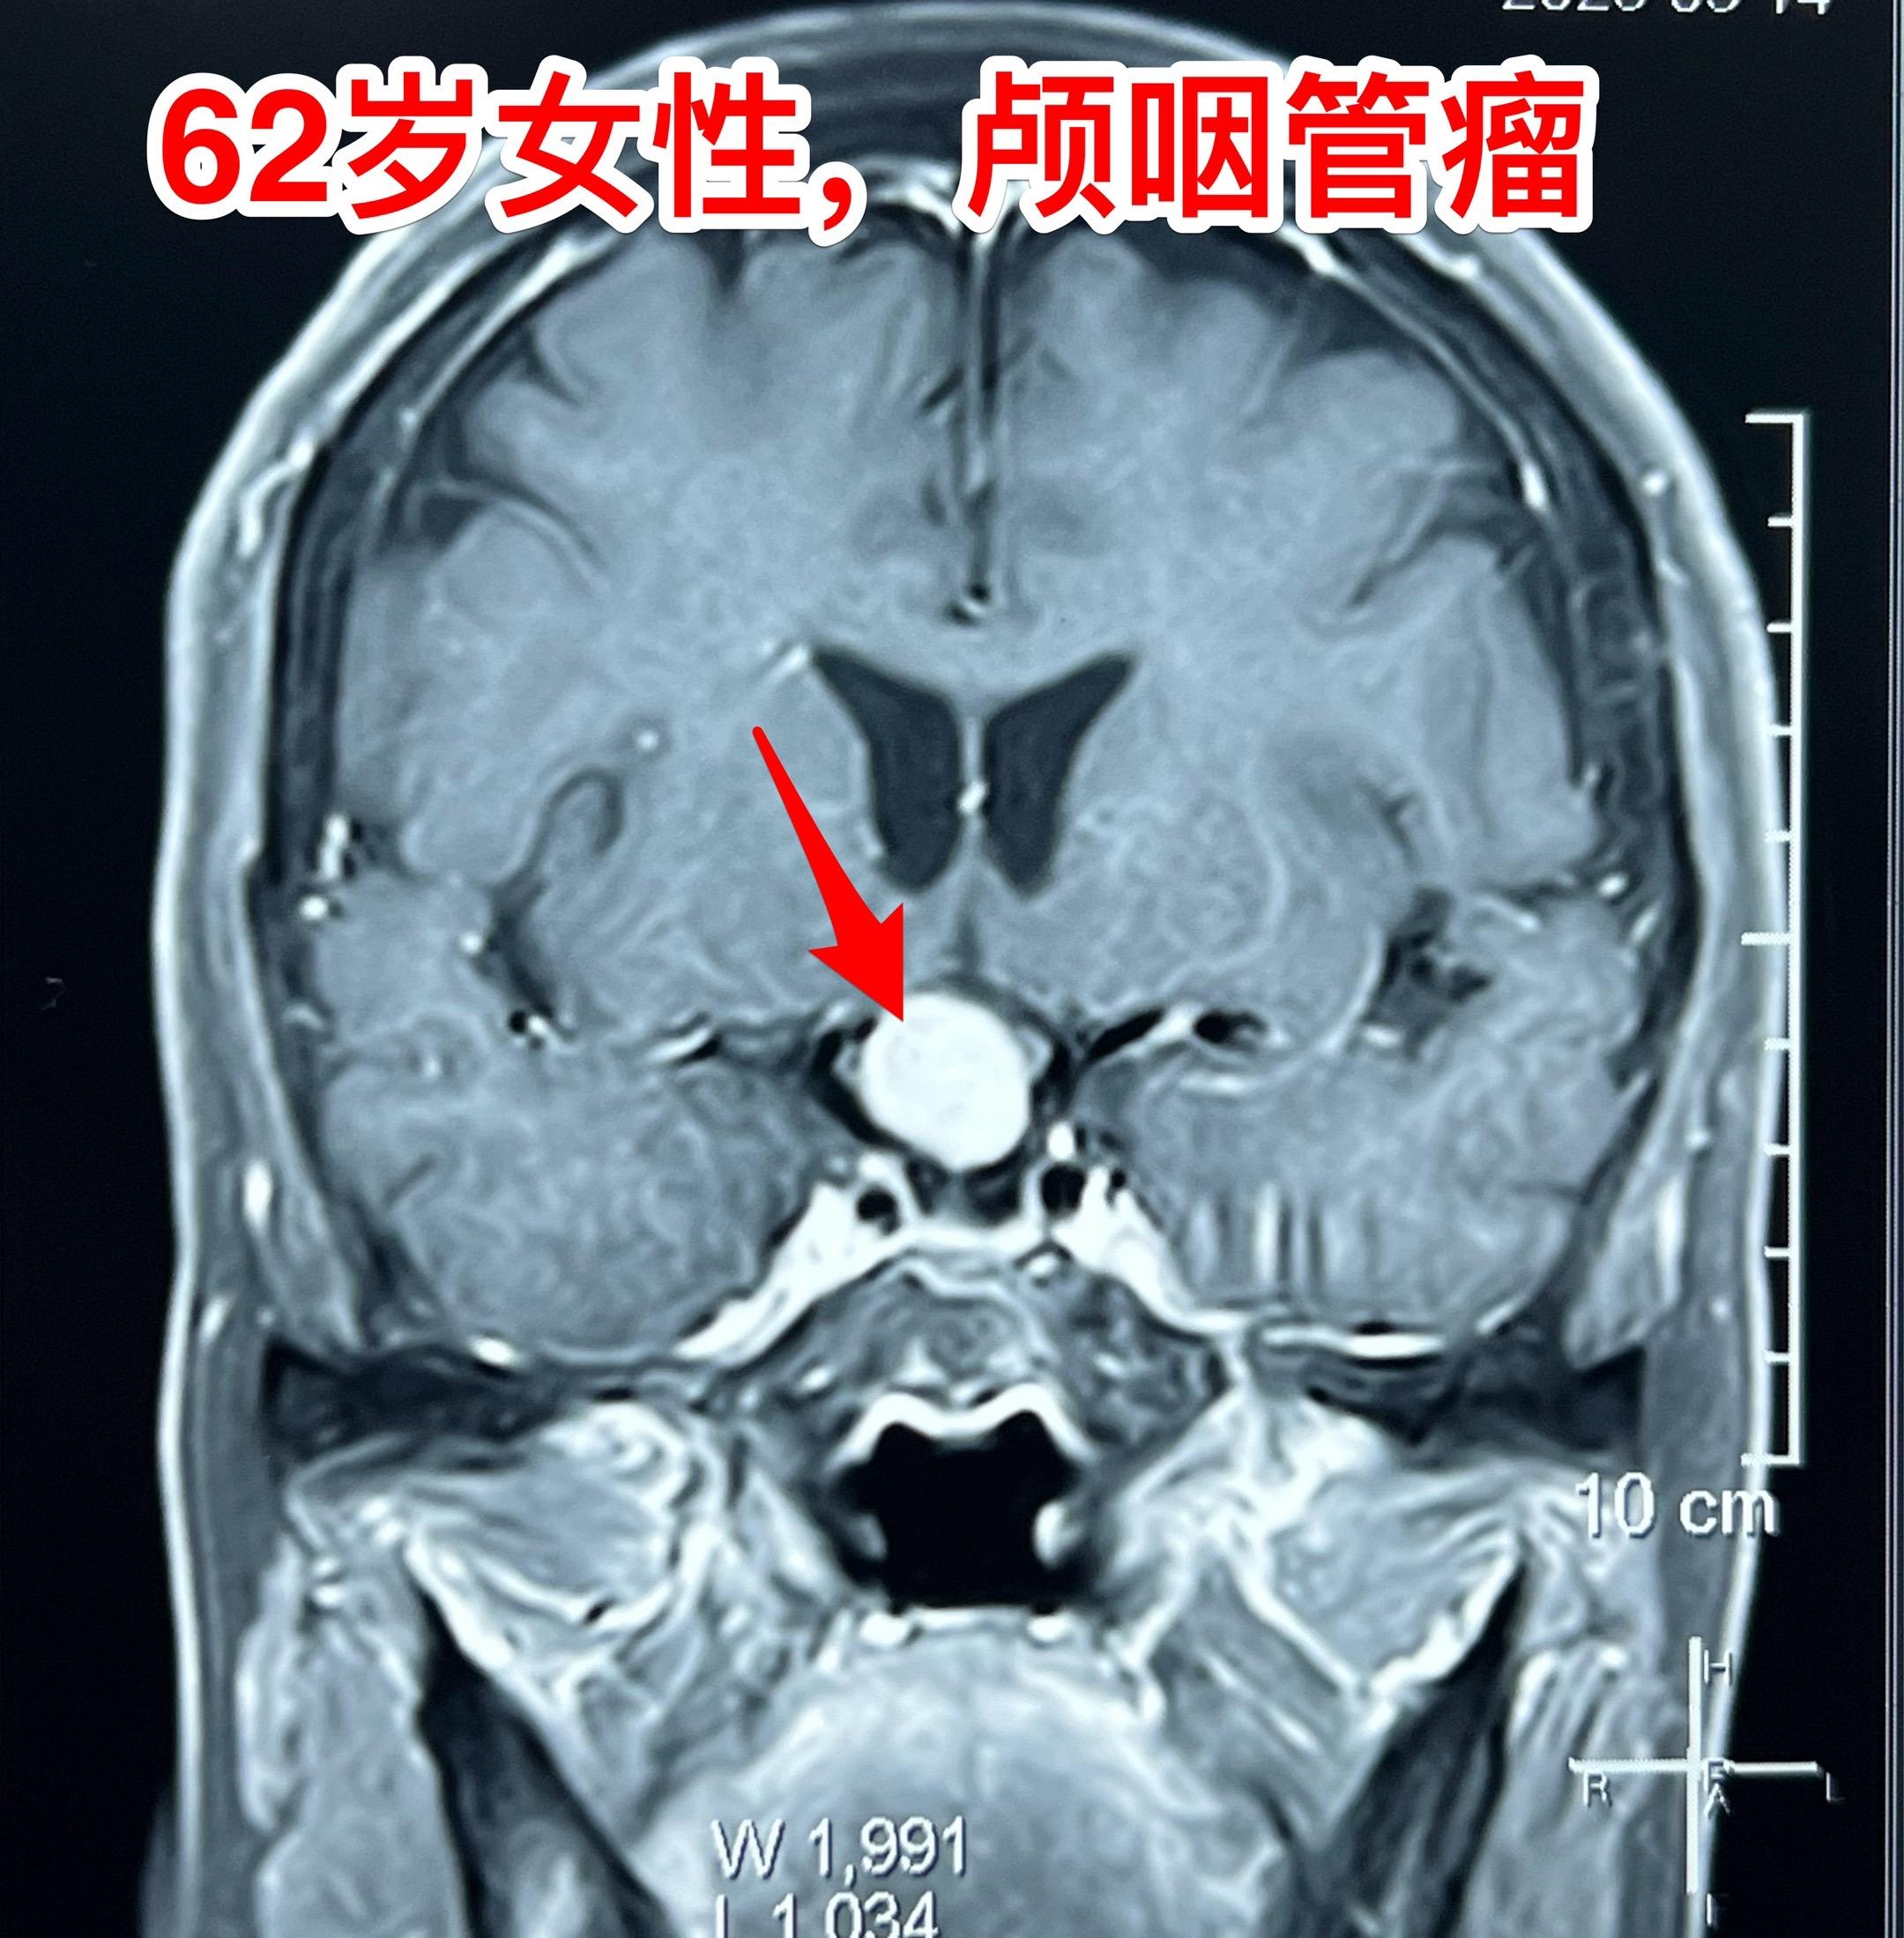

经翼点入路切除颅咽管瘤-不能忘记的入路 经翼点入路切除颅咽管瘤,曾经是广泛使用的一种入路,当然有其优点。近十几年使用这个入路切除颅咽管瘤的机会大大减少了。 对于比较小的鞍上型颅咽管瘤或者自中线偏向侧裂池方向生长的颅咽管瘤,这个入路是很适合的。 3月21日为62岁女性病人切除颅咽管瘤,采用的就是经翼点入路。肿瘤得到完全切除,垂体柄得到保护[强]